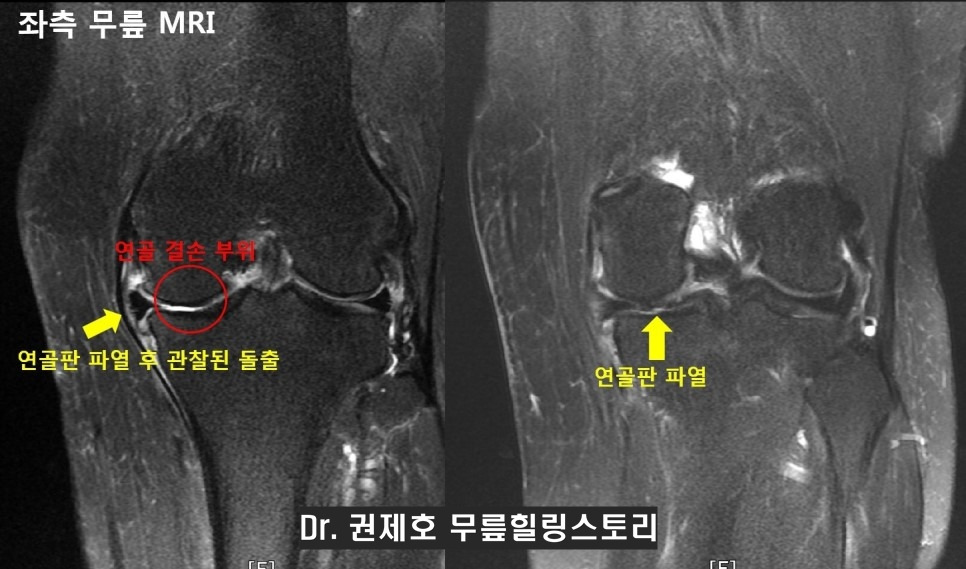

평소에 등산을 즐겨하시는 54세 여자 환자분으로, 내원 약 1달전 등산한 후 내려오시던 중, 좌측 무릎 내측(안쪽)으로 뜨끔한 통증과 함께 무릎이 붓고 통증이 심해서 작은 병원에서 약물 복용, 물리치료, 주사치료 시행하였으나 통증의 완화가 없던 분으로 병원에 오셨을 때 이학적 검진상 무릎 내측(안쪽)에 압통(누르면 아프다)이 있으면서 무릎이 많이 부어 있어서 불가피하게 정밀검사(MRI)를 시행 하하였다.

검사상 안쪽 연골이 깨지고 연골판이 찢어져서 연골이 돌출되어 있어서 수술적 치료를 시행하게 되었습니다. 수술방법으로 고려하여야 할 것 중 가장 중요한 것이 바로 다리 정렬 검사입니다.